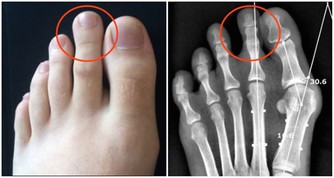

氨基酸是構成蛋白質的基本單位,有研究表明,老年人與中青年人相比,在同等的營養條件下,老年人的支鏈氨基酸減低得更為明顯,這直接影響身體肌肉量。